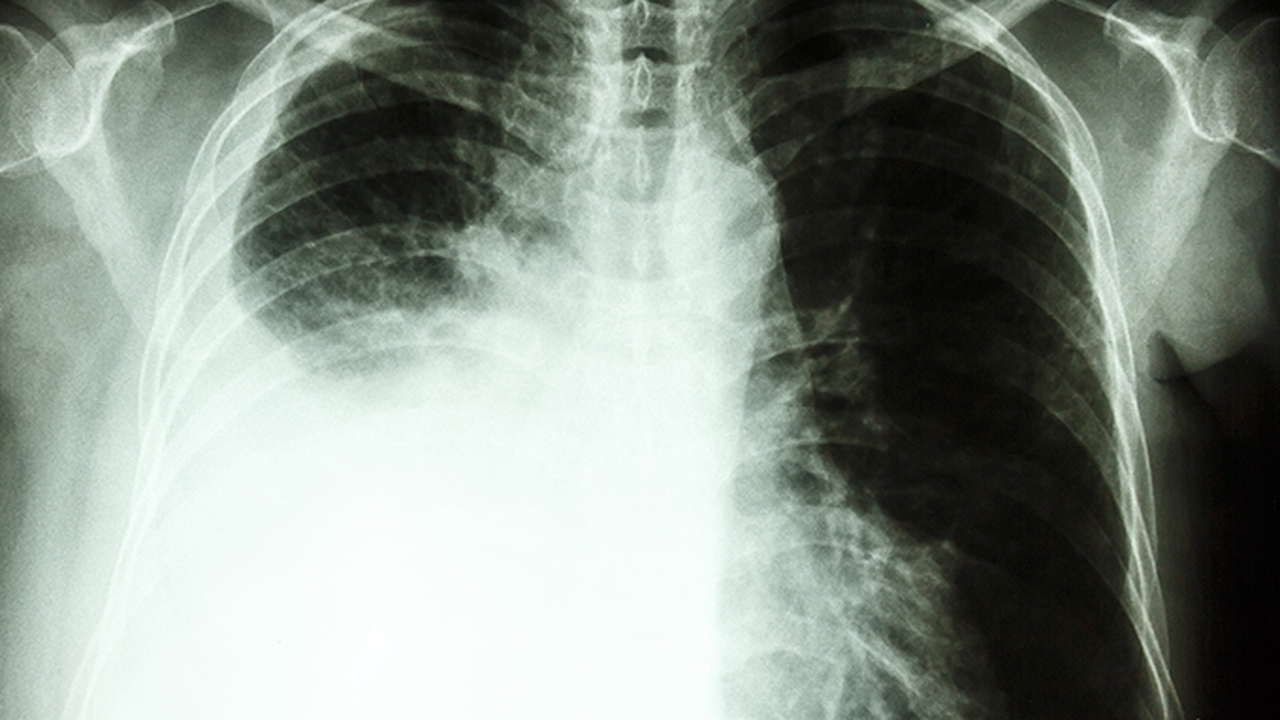

肺气肿是一种常见的慢性呼吸系统疾病,主要表现为肺泡壁破坏、肺弹性减弱,导致呼吸困难等症状。其发病原因多样,包括长期吸烟、空气污染、职业粉尘暴露等。早期诊断和规范治疗对延缓病情进展至关重要。